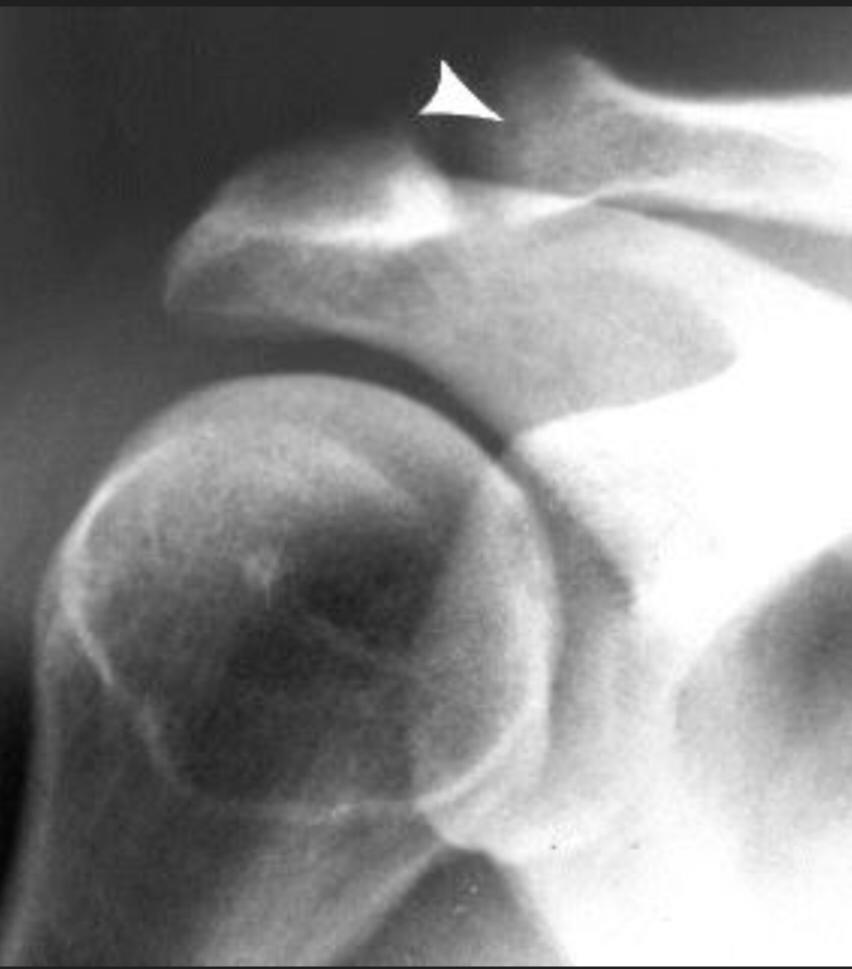

Distal clavicle osteolysis is a unique disease most likely due to an overuse phenomenon. Distal clavicular osteolysis (DCO) follows both chronic repetitive stress and single acromioclavicular trauma. Acute distal clavicular osteolysis was first described in 1936.

The exact aetiopathogenesis is unclear, but AC-joint trauma and subchondral microfractures seem to be involved. Subsequent attempts at repair are insufficient and the final result is osteolysis. It is unclear why changes predominate in the distal clavicle while the acromion is relatively spared.)

Mostly affected males in their 20s and commonly seen in weightlifters, symptoms usually begin with an insidious aching pain in the AC region that is exacerbated by weight training. Clinical findings are often nonspecific and frequently overlap with those of labral or rotator cuff tears. On examination, patients have point tenderness over the affected AC joint and pain with a cross-body adduction maneuver.

Conventional radiographs may remain normal during the first months or years. A 15° cephalad inclination avoids superposition of the scapular spine with the AC-joint (Zanca view).

Radiographic changes include cortical thinning, irregularity and microcysts in distal clavicle and mild AC–joint widening. A late finding is tapering of the distal clavicle.

MRI is far more sensitive to detect DCO in an early stage. The most common MR-finding is bone marrow oedema in the distal clavicle, sometimes also in the articular part of the acromion, but less distinct.

Often, a hypointense line is seen in this area of clavicular bone marrow oedema, representing a subchondral fracture. AC-joint abnormalities are common, and include effusion, mild widening, intra-articular bone fragments and capsule hypertrophy. Other MR-findings are similar to those seen on radiographs, as described above.

Bone scan may also shows increased uptake in the distal clavicle, which could be seen earlier than radiographic changes.

Treatment is essentially conservative, consisting of rest and nonsteroidal anti-inflammatory drugs (NSAID's), and is usually successful. In severe cases, resection of the distal clavicle is indicated. If left untreated, the process may cause progressive resorption of lateral aspect of the clavicle, erosions and cupping of the acromion and dystrophic calcifications.

DCO should be considered in the differential diagnosis of shoulder pain in the appropriate population. Therefore, analysis of MR arthrographic studies of the shoulder should not be restricted to evaluation of the rotator cuff and capsulolabral system, but the AC-joint should be scrutinised as well.